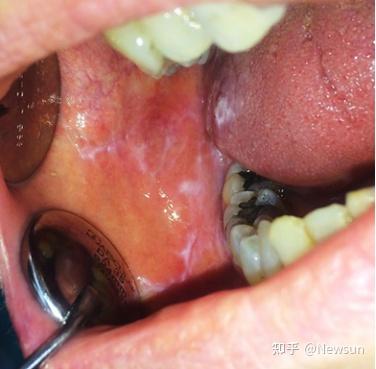

• 扁平苔藓与白塞氏病的特征表现及病因分析 扁平苔藓与白塞氏病的特征表现及病因分析

• 口腔扁平苔藓与白塞氏病 症状、诊断与治疗全解析 口腔扁平苔藓与白塞氏病 症状、诊断与治疗全解析